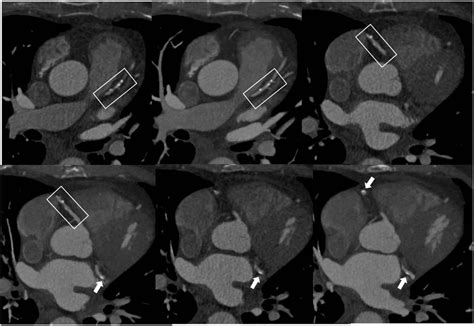

The Significance of Coronary Artery Calcification for Percutaneous ...

4415Γ—1491